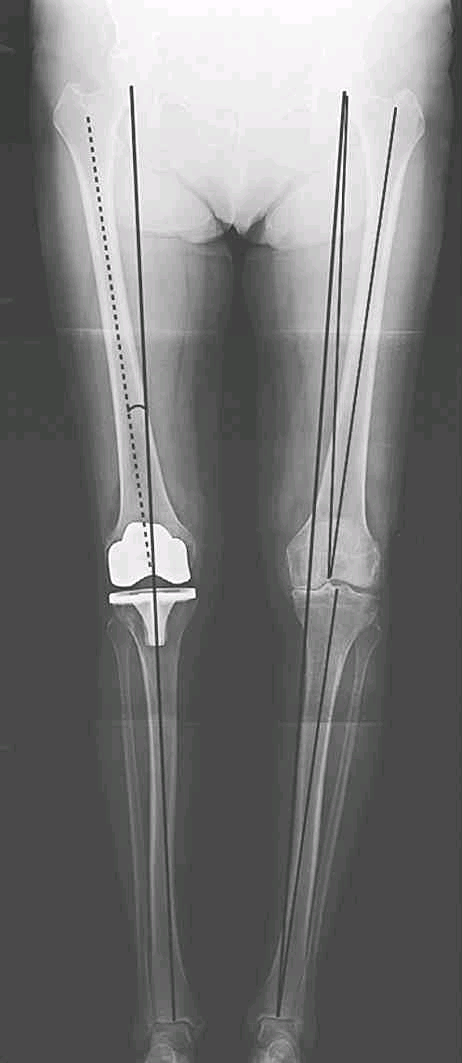

下肢轴线:

右下肢为关节置换术后,下肢力线与胫骨机械轴重叠;左下肢为未置换,下肢对线不良,膝关节内翻

(1)下肢机械轴(mechanical axis of the lower extremity):

也称下肢力线,即股骨头中心至踝关节中心的连线。假如该线经过膝关节中心点,则股骨机械轴将与胫骨机械轴相重叠。

(2)股骨机械轴(mechanical axis of the femur):

股骨头中心至膝关节中心的连线。

(3)股骨解剖轴(anatomic aixs of the femur):

股骨髓腔中心纵轴线。

(4)胫骨机械轴(mechanical axis of the tibia):

膝关节中心至踝关节中心的连线。